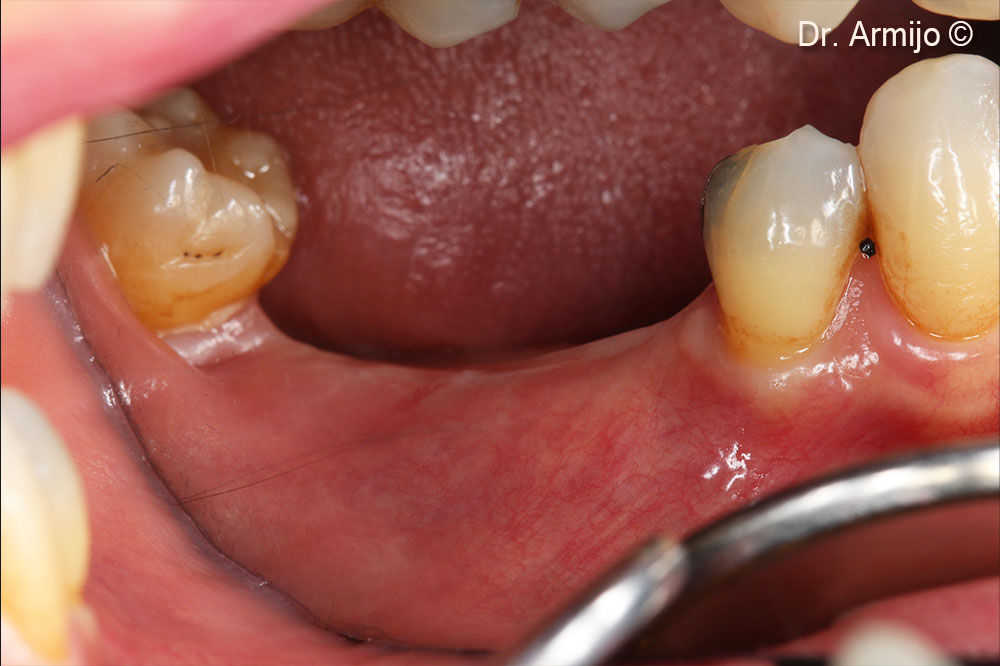

Initial clinical image (note the vertical defect).